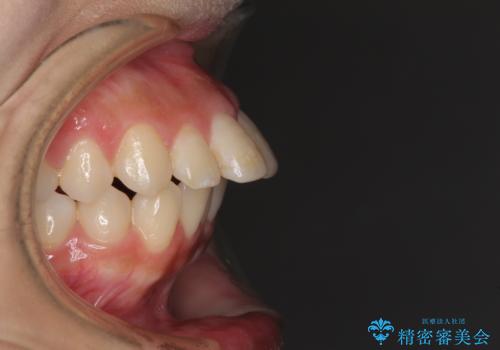

突出した口元が気になる ハーフリンガル装置による抜歯矯正

- 口元の突出感を気にして来院された患者様です。

通常では上下左右の第一小臼歯4本を抜歯しますが、下顎が左側にシフトしていたため、下顎左側のみ第二小臼歯を抜歯し、正中を合わせながら口元を下げる治療計画としました。